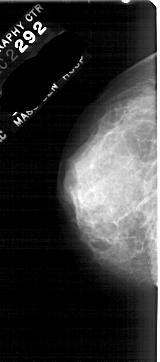

A_1746_1.LEFT_CC

LEFT_CC LINES 5056 PIXELS_PER_LINE 2236 BITS_PER_PIXEL 12 RESOLUTION 43.5 NON_OVERLAY